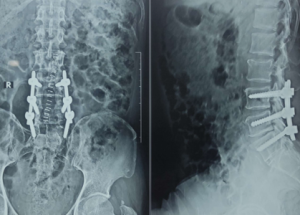

Expert spine services including minimally invasive surgery, pain management, and deformity correction.